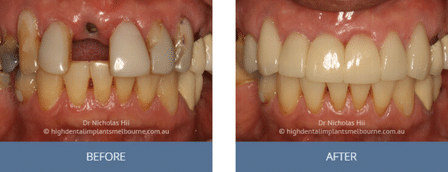

Clinical Before and After Photos

At High Dental, we believe a great smile changes everything. Our Smile Gallery showcases before-and-after images of patients who trusted us with their smiles. From veneers and crowns to full-arch implants, each result is unique — and each started with a consultation. Scroll through and imagine the possibilities for your own smile.

Images are provided for illustrative purposes only. Results shown relate to specific patients and individual outcomes may vary. A consultation is required to determine suitability for treatment.